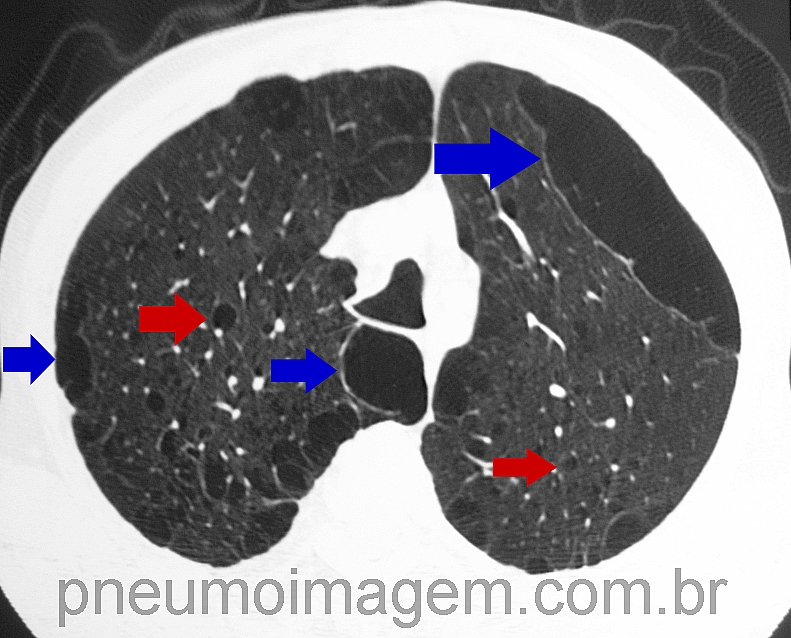

O objetivo do ensaio foi avaliar se os achados tomográficos incidentais de enfisema, espessamento das vias aéreas e bronquiectasias, vistos nas tomografias realizadas para outras indicações clínicas não-pulmonares, estão associados com futuras exacerbações agudas de DPOC que resultaram em hospitalização ou morte.

Esse estudo prospectivo multicêntrico avaliou 6406 indivíduos durante um período de acompanhamento médio de 4,4 anos (máximo de 5,2 anos). Foram identificados 338 eventos de DPOC. O risco de sofrer uma exacerbação aguda futura da doença que resultou em hospitalização ou morte foi significativamente aumentada em indivíduos com enfisema grave e espessamento das vias aéreas grave. Os respectivos HRs foram de 4,6 (IC 95% 3,0-7,1) e 5,9 (IC 95% 3,4-10,5). Bronquiectasias graves (pontuação ≥3) não foram significativamente associadas com o aumento do risco de eventos adversos (HR 1,5; IC95% 0,9-2,5).

Os autores concluíram que os achados morfológicos de DPOC detectados pela tomografia computadorizada realizada para outras indicações não-pulmonares, como espessamento das vias aéreas e enfisema, são fortes preditores independentes de desenvolvimento posterior de exacerbações agudas de DPOC que resultaram em hospitalização ou morte.